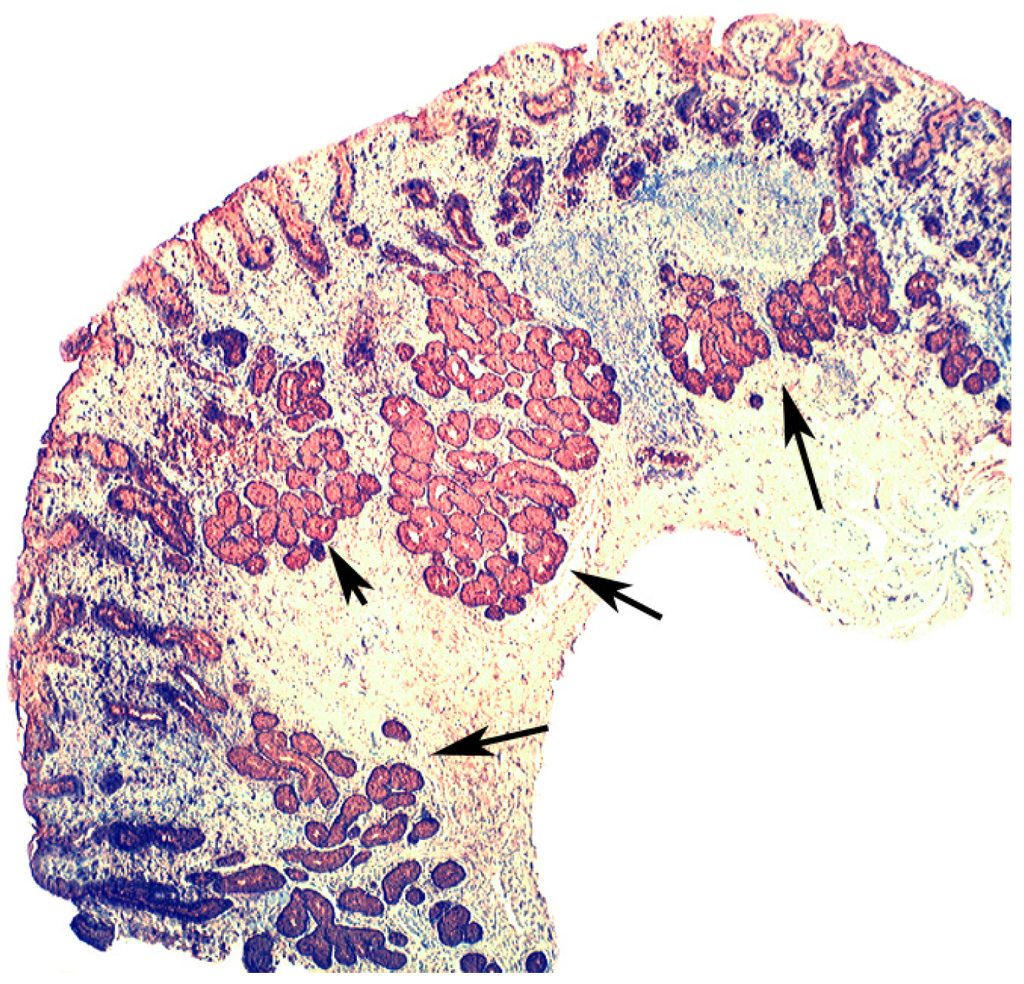

In chronic gastritis lysozyme is up-regulated in the neck region of the oxyntic mucosa, in antral pyloric glands (Figure 5) and in the surface-foveolar epithelium of the oxyntic mucosa [8]. In cases with in intestinal metaplasia, lysozyme is up-regulated in goblet cells (Figure 6), and in Paneth cells. In cases with autoimmune gastritis, lysozyme is up-regulated in pseudo-pyloric glands (Figure 7).

Figure 7.

Autoimmune gastritis (corpus) showing lysozyme expression in pseudopyloric glands at arrows (lysozyme immuno-stain, ×4).